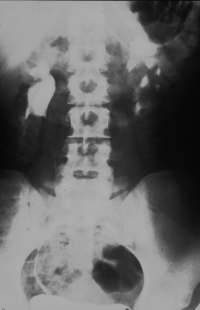

• Abbildung 17: Ureterabgangsstenose mit ausgedehnter Hydronephrose links

1. Ausscheidungsurogramm stumme Niere links (schwacher nephrographischer Effekt)